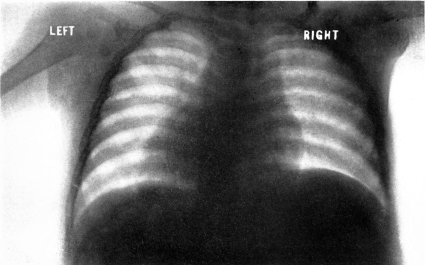

| 19. | Scorbutic beading of ribs. Roentgenogram | 198 |

| 20. | “White line.” Roentgenogram | 199 |